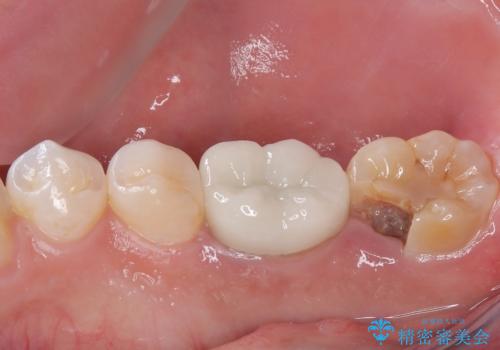

審美面、機能面共に満足していただけました。

舌側の虫歯が大きかったため歯茎の腫れが心配でしたが腫れもなく経過良好です。

引き続き矯正後の後戻りのチェックを行っていく予定です。